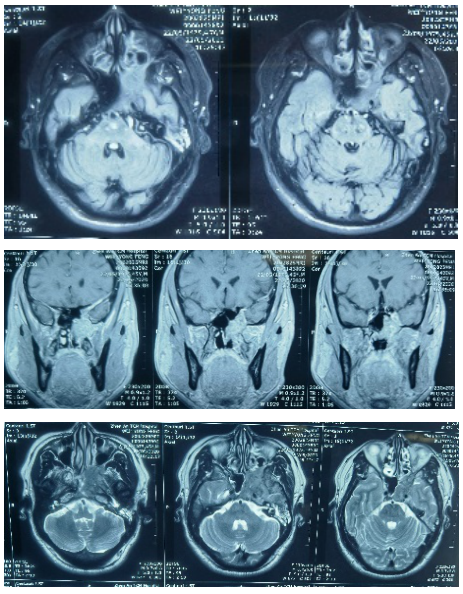

影像学检查:

颈部MRI(镇安县中医医院,2020-5-22): 鼻咽顶部及左侧鞍旁不规则肿块影并周围骨质多发破坏及左侧咽旁间隙、颈外侧区多发淋巴结肿大,考虑恶性占位性病变。